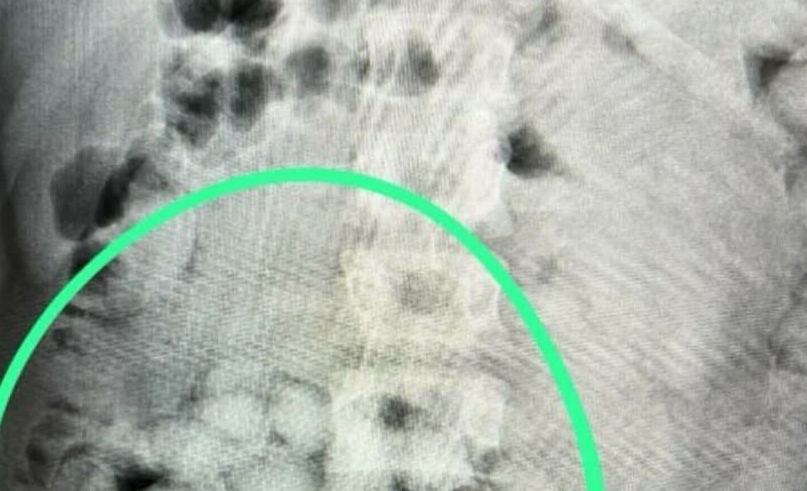

De asemenea, la controlul cu un scanner cu raze X poliţiştii au văzut, în stomacul bărbatului, „formaţiuni neobişnuite” pentru anatomia umană.

În urma controlului efectuat cu ajutorul unui scaner cu raze X, în interiorul abdomenului bărbatului au fost observate mai multe formaţiuni neobişnuite, care nu corespund anatomiei umane.